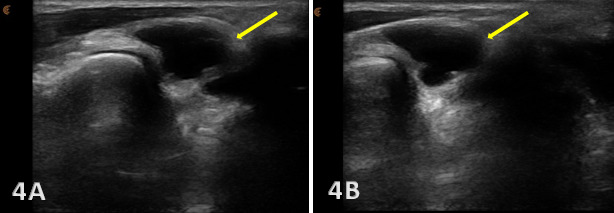

Associated joint effusion and/or synovitis (synovial hypertrophy) and cysts. Joint effusion will appear as anechoic or hypoechoic fluid within the DRUJ or TFCC area. Joint effusion is somewhat compressible and mobile when transducer pressure is applied to the area. This is different from synovitis, which appears as hypoechoic or isoechoic, non-compressible tissue within the joint recess. Lastly, a ganglion cyst will appear as a well-defined, round or lobulated cystic structure with anechoic or hypoechoic internal contents. The cyst typically has a small, smooth wall and exhibits posterior acoustic enhancement. These cysts will typically be minimally or non-compressible and painful.

Anechoic or hypoechoic fluid indicating effusion in the joint.

Excessive translation of the ulna relative to the radius during dynamic visualization of the movements of pronation and supination may indicate DRUJ instability.

A bony avulsion of the ulnar styloid attachment site would be indicative of an associated peripheral TFCC tear.